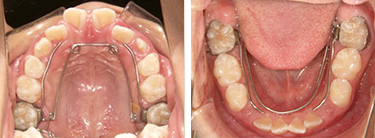

Step3: モノブロック装置(就寝時)

| 行ったご提案・診断内容 | 成長期にアーチ形態の修正・拡大(QH・BH)で永久歯の萌出スペースをつくり、上下前歯の調整(ブラケット)を行いました。舌などの機能改善はMFTで行いました。 咬合治療はモノブロック装置を先行させ、必要によりマルチブラケット法へ移行予定です。 |